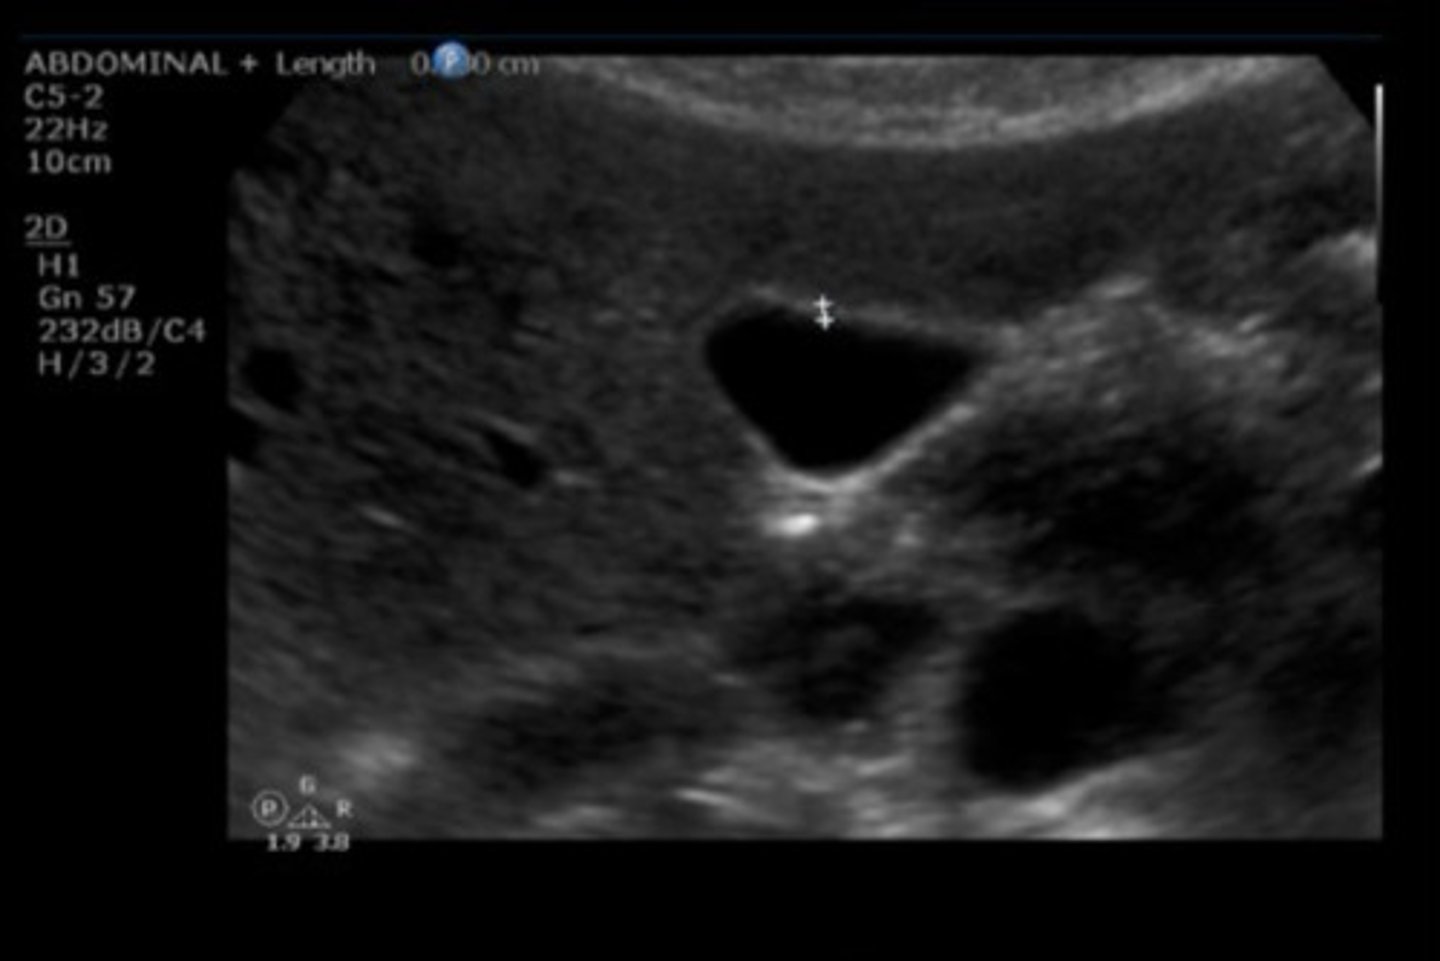

11

New cards

CBD

Identify the following;

<p>Identify the following;</p>